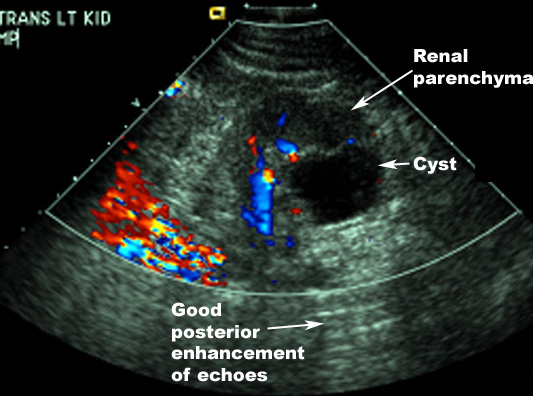

Renal Masses are often detected as an incidental finding on KUB or IVP.  Ultrasound would be the first test of choice to characterize the mass since no IV contrast or radiation is used. It is ideal for children, pregnant women and patients with renal failure. If the lesion is clearly cystic, no further test is necessary. If solid, contrast CT should be done.

Ultrasound characteristics: